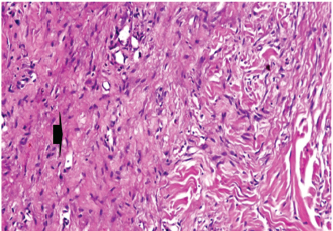

Histopathological findings of wound healing

At 7 days post wounding; the inflammatory reaction was moderate and characterized by polymorphonuclear cells and macrophages infiltration with the presence of small scab covering the wound surface. Early evidence of epithelization was detected and represented by the proliferation of epidermal epithelium under the scab. There was marked thickening and hyperplastic proliferation of epidermal epithelium at the free wound edge (Fig. 6). The dermal tissue underlying the wound area showed few polymorphonuclear cells infiltration and more abundant mononuclear cells. Fibroplasia and angiogenesis were detected in the dermis and more extensive in deeper areas of the dermis which characterized by fibroblast and angioblast proliferation forming immature young granulation tissue (Fig. 7). At 14 days post wounding, the wound area was covered by a complete layer of epidermal epithelium indicating a good epithelization rate of the wound. Proliferation of cutaneous appendages was detected. The newly formed epithelium was thick and showed partial keratinization and epithelial differentiated stratum containing polyhedral keratinocyte with the appearance of keratohyalin granules in their cytoplasm (Fig. 8). The dermal tissue showed deposition of parallel well organized and interconnected collagen bundles that arranged parallel to epidermis associated with enhanced angiogenesis represented by well-developed blood capillaries (Fig. 9). At 21 days post wounding, remodeling of the formed epithelium with relatively small scar formation and mild restoration of skin appendages. Keratinized and differentiated stratum comprising the covering epithelium and the newly formed skin appendages from the basal epidermal epithelium were detected (Fig. 10). The dermal tissue revealed well-formed organized tissue consisted of parallel compact and interconnected bundles of collagen with scant angiogenesis (Fig. 11). At 28 days post wounding, well-formed scar tissue covering highly cellular organized tissue was detected (Fig. 12). The dermal tissue revealed well-arranged compact collagen bundles containing scarce blood vessels (Fig. 13).

Fig. 6. Skin of a goat from electroacupuncture group at 7 days post wounding showing early evidence of epithelization, hyperplastic proliferation of epidermal epithelium (arrow head) at the free wound edge, and moderate inflammatory cells infiltrations in the dermis (arrow), (HE ×100).

Fig. 7. Skin of a goat from electroacupuncture group at 7 days post wounding showing fibrin exudation at wound surface with dermal edema, hemorrhages (arrow) with moderate mononuclear cells infiltration associated with formation of immature granulation tissue consisted of fibroblast and angioblast forming small blood channels (arrow head), (HE ×200).